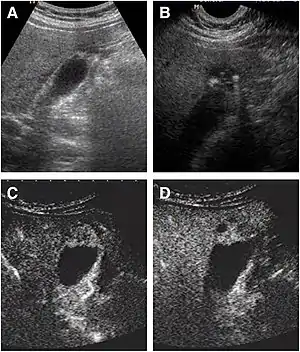

a The fundus of the gallbladder wall was thickened and the GB wall was obscure.

b The intramural echogenic foci were detected by high frequency transducer.

c CEUS—arterial phase (22 s) —heterogeneous hyper-enhancement and wall was intact.

d CEUS—venous phase (34 s) the anechoic spaces were more clear.

Abdominal ultrasound has low accuracy in differentiating gall bladder adenomyomatosis from cancer and is operator dependent. However, it is used as the exam of the first-line due to its wide availability. Ultrasound findings may show thickened gall bladder wall, tiny anechoic spaces (Rokitansky–Aschoff sinuses or RAS), and twinkling artifact (or comet-tail reverberation). Comet tail reverberation, which is due to reflections from cholesterol crystals, is a highly specific sign for adenomyomatosis.[8]